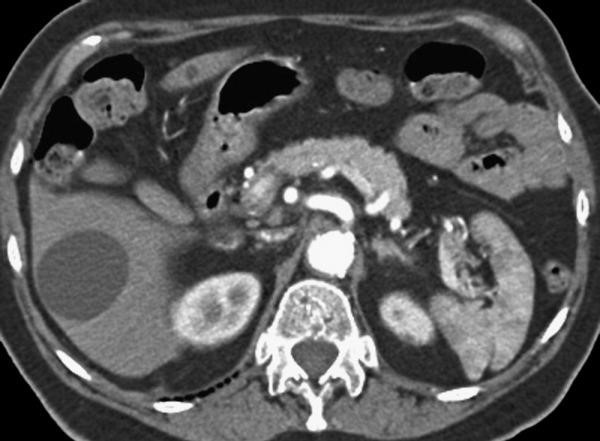

• Triple-phase helical CT scan

• The presence of arterial enhancement followed by washout has a sensitivity and specificity of 90% and 95%, respectively.

• Diagnosis: imaging or FNAC.